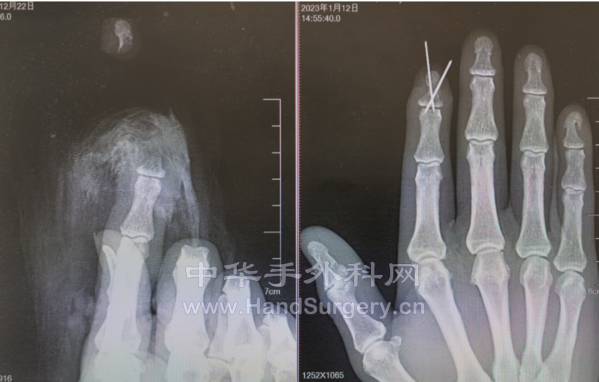

本帖最后由 zhangwenlong 于 2023-1-16 19:55 编辑

两个阳性大夫,两个阳性护士,一个阳性麻醉师,给一个阳性病人做手术。手术室里除了监护仪的心跳声,就是此起彼伏的咳嗦声……

IMG_20230112_154436.jpg